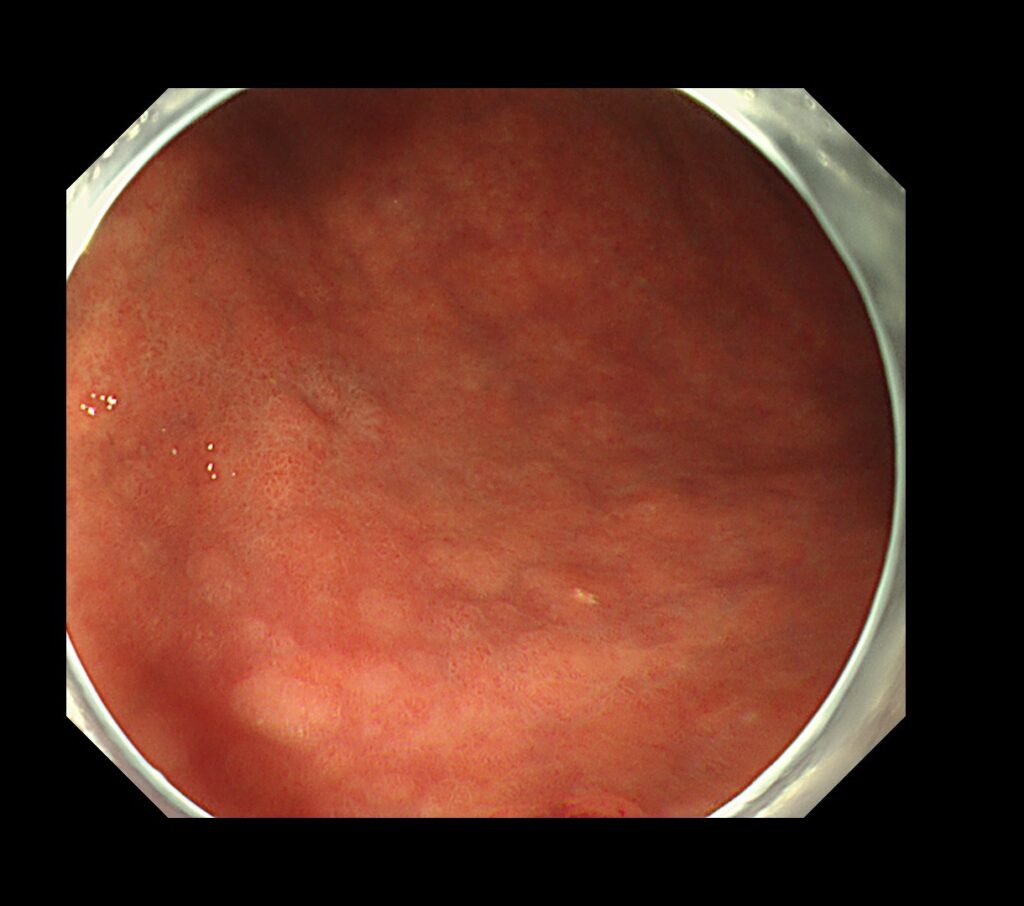

胃の下部の病変です。通常観察では、局在診断が困難な症例です。

さて、どこに病変があるでしょうか?